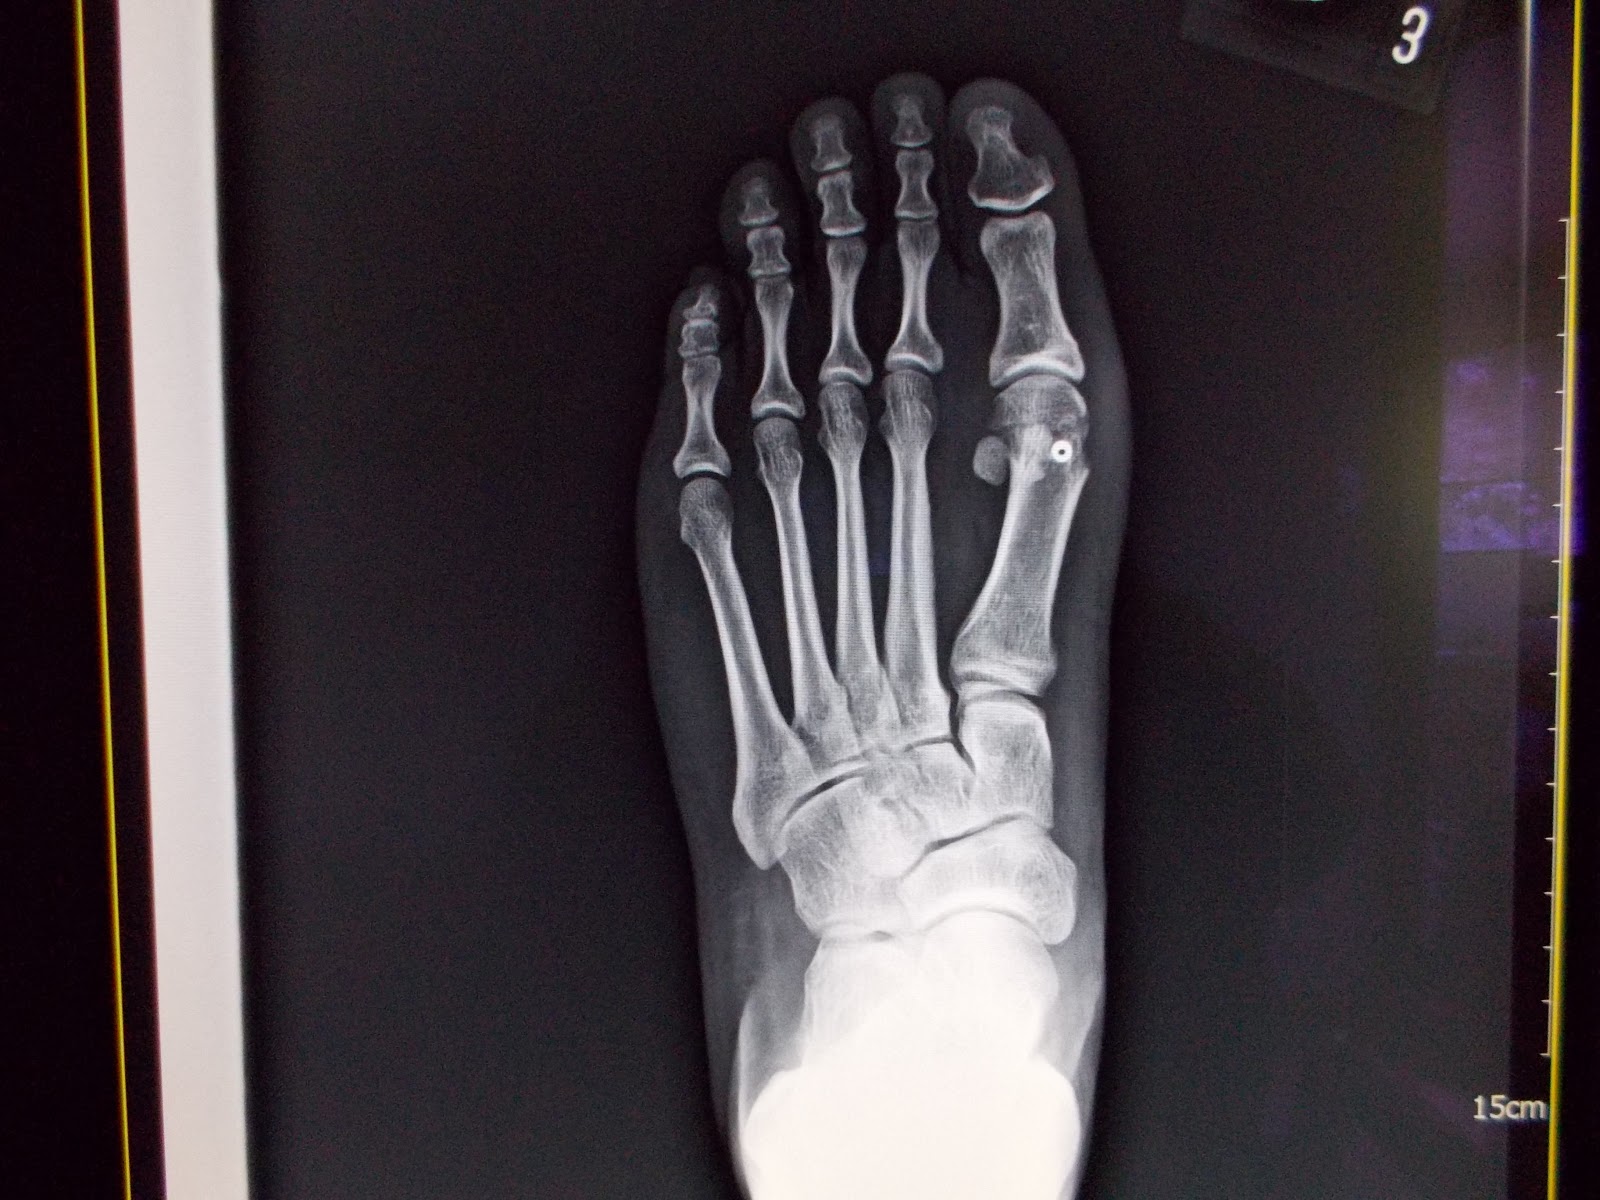

太緊的內收肌 肌腱,把大拇趾慢慢的向外拉,趾蹠關節也被拉成脫臼,產生關節滑液囊腫(即常稱的Bunion);或頂起鄰(第2)趾、或造成足底胼胝(雞眼),讓腳久站、走路、穿鞋疼痛。診斷上,除了看外觀外,還須照X-光,仔細評量趾-蹠交角、蹠-蹠交角的度數;趾-蹠關節 對位情形,及蹠底芝麻骨 (有2個) 脫位的程度……等,作為是否須手術治療的憑估。雖然,坊間有各式各樣的護具、矽膠墊、…..宣稱可復健矯正,但實際上沒有真正的效果,矯正還是要靠手術。

手術主要是作蹠底內收蹠肌 肌腱的鬆筋術,以消除肌腱的不當拉(張)力;在大部份年青小姐、早期外翻 (趾蹠骨交角)不厲害,鬆筋手術即有很好效果(圖3.)。

但設若外翻變形厲害,趾蹠關節也退化變形,則還須加上切骨矯正術(如圖4-5-6),術後 頭2週用拐杖助行,